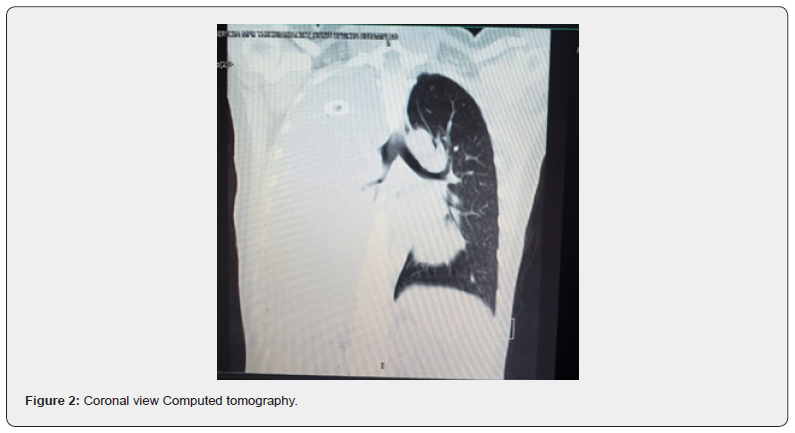

One month later she came to ED in the same health center with the same symptoms, on physical examination there is dullness on percussion on the right hemithorax. The attending physician order an X Ray, and a pleural effusion vs empyema is suspected, a chest tube is placed on the right hemithorax but there is not exudate drain (Figure 1). A CT scan without contrast report liquid density of 100% of right hemithorax UH between 2-38 multiples loculations and septum that produced atelectasis and displaced mediastinal structures. It was not possible to determine the size of the anterior mediastinal mass (Figure 2).

On the emergency anesthesia evaluation, reviewing the images it was determined that the trachea is displaced at principal bronchi level, and unipulmonar ventilation will be necessary, but there is not a direct compromised of the airway.